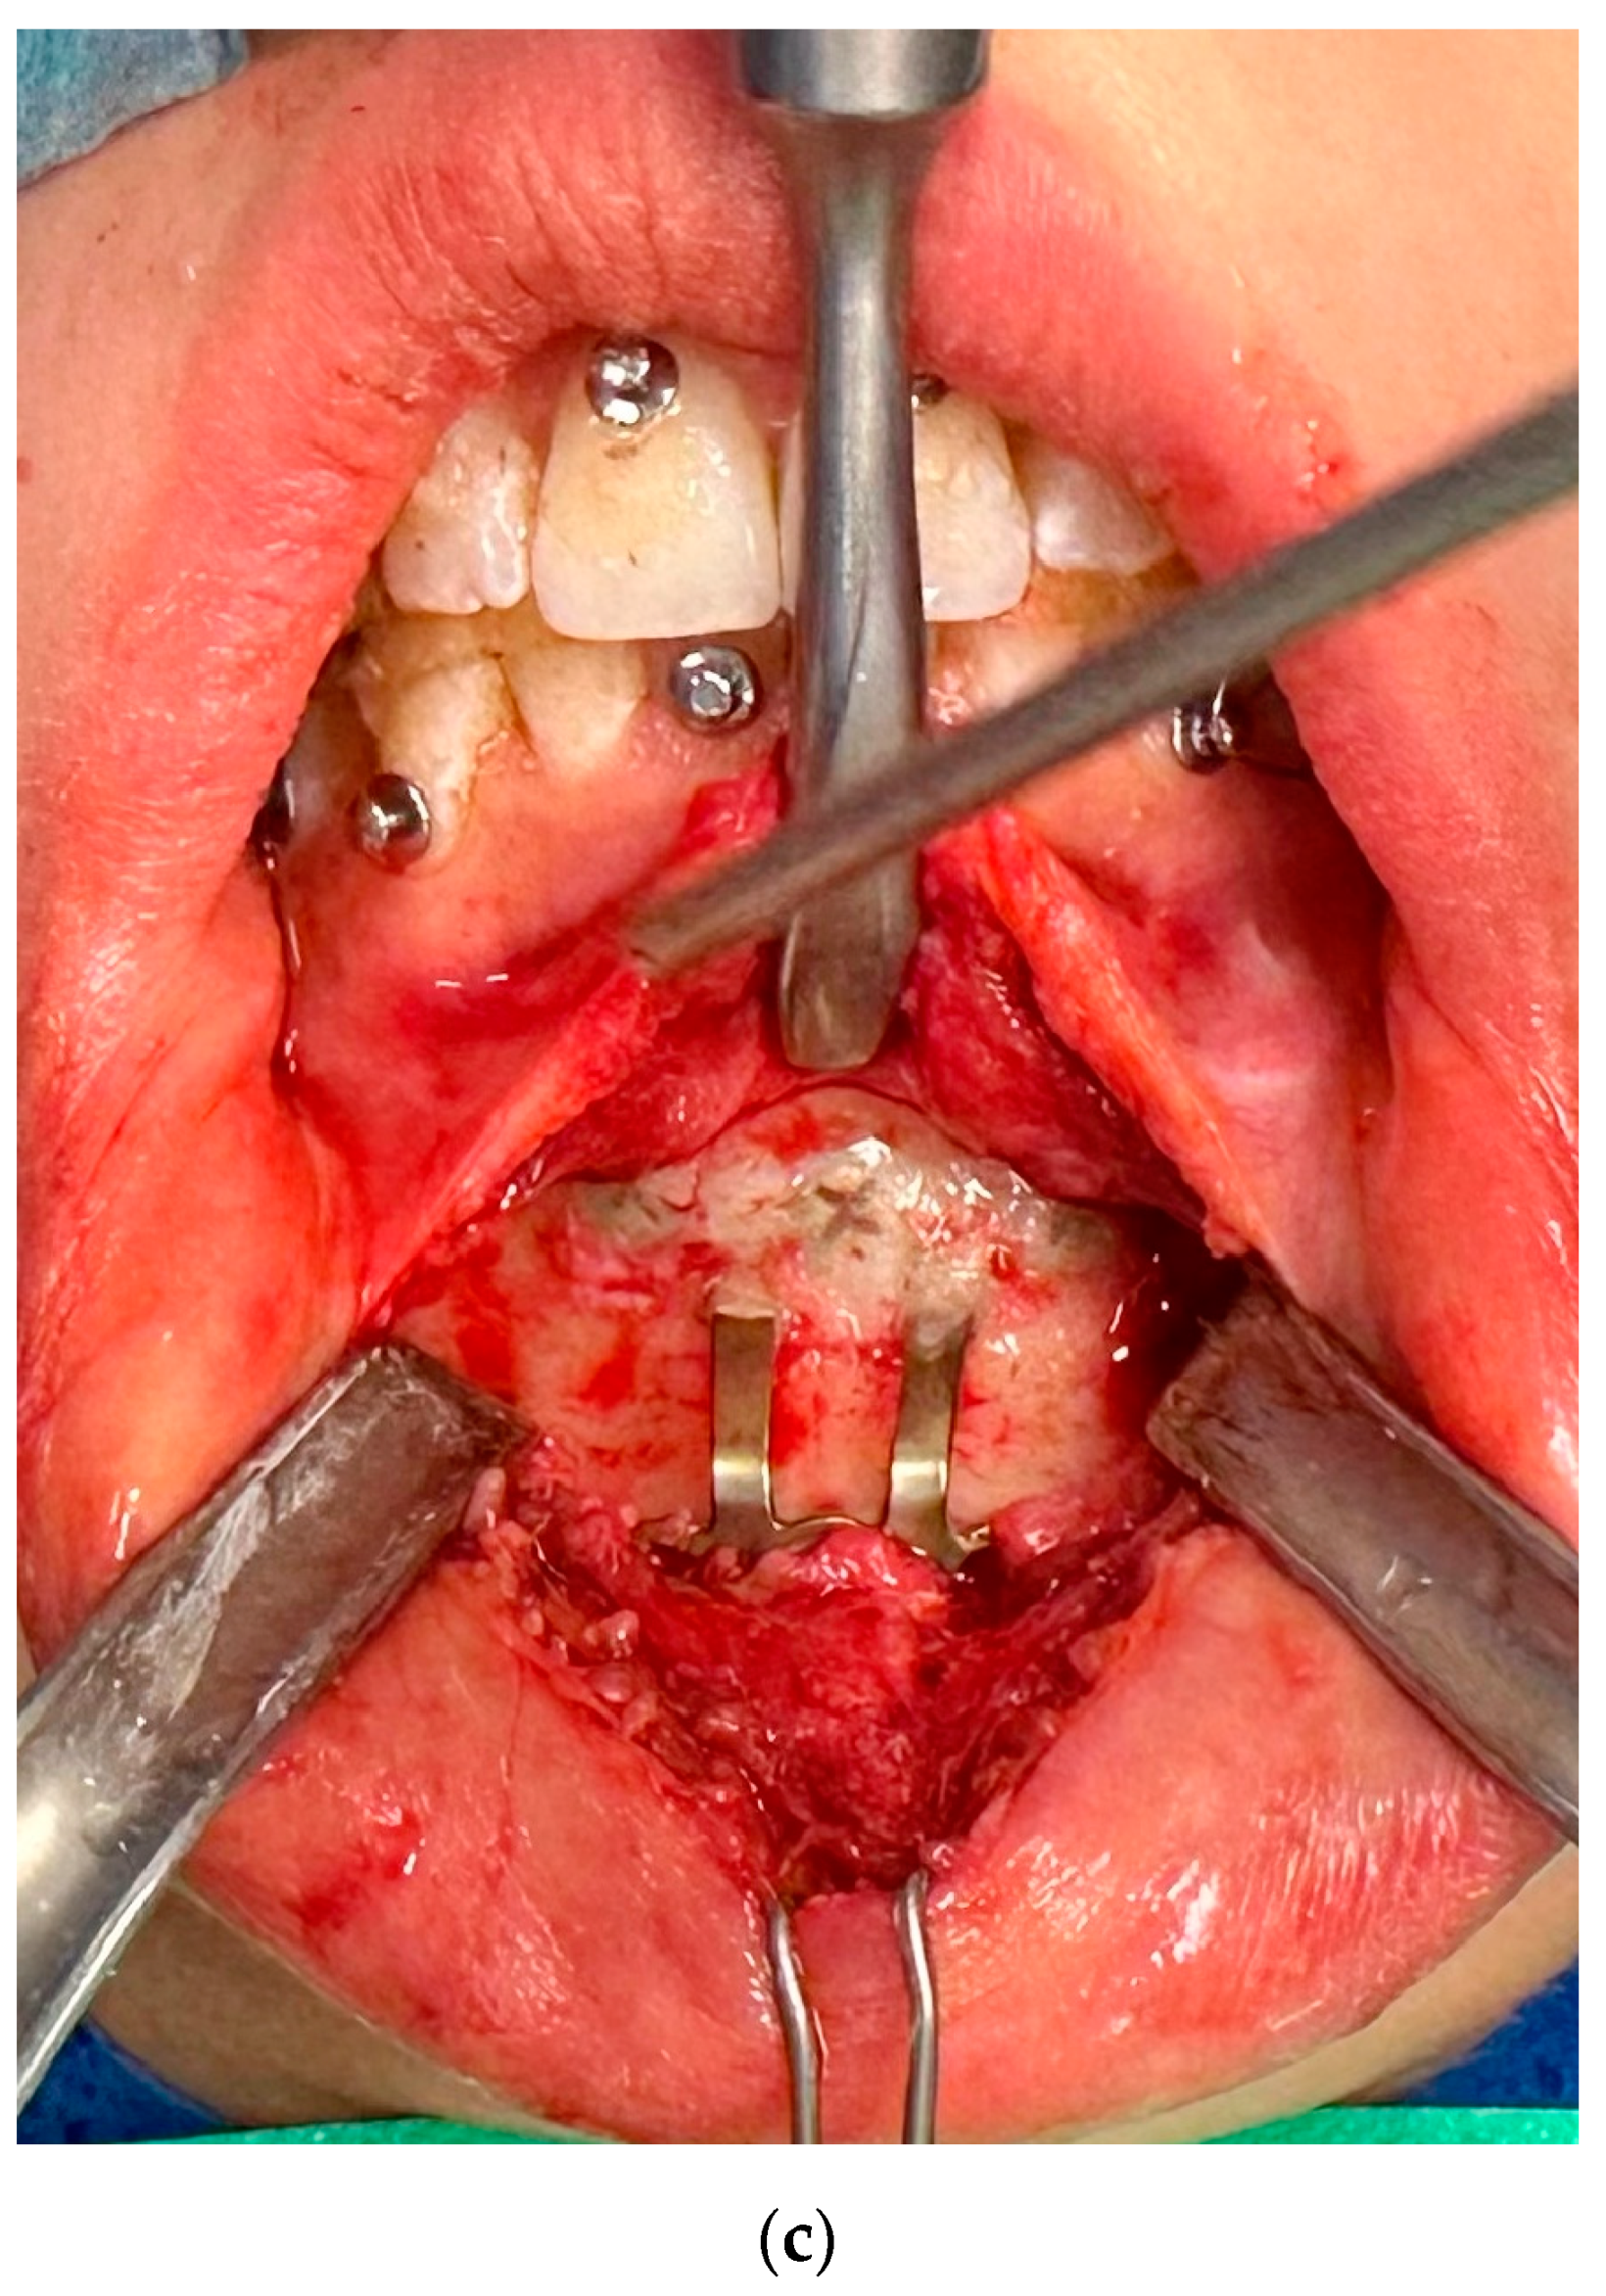

The first group included complications such as the occurrence of inflammation, infection, and fistula in the fixation area, swelling, or fixation exposure (Figure 2). This occurred in 17 cases, representing 22.08% of 77 fixation hardware removal procedures and 11.97% of 124 orthognathic procedures performed.

Figure 2.

Image of inflammation/infection: (a) intraoral photo with fistula in the fixation area; (b) CBCT mandibular screws not fixed due to inflammation; (c) CBCT osteonecrosis in the bicortical screw area.

In instances of inflammatory complications or infections, the affected area in 11 cases was the maxilla and in 6 cases it was the mandible.

In 4 of 17 cases where complications were the reason for osteosynthesis removal, only the hardware that caused the problem was removed, and in the remaining 13 cases, all fixation hardware was removed at the same time.